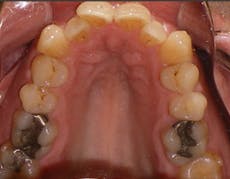

Figure 3: 36 mm is an appropriate width; the others display improper width and insufficient tongue space. Photos courtesy Dr. Ben Miraglia.

36 mm

30 mm

32 mm

25 mm

As the transverse measurement decreases, so does the “home” for the tongue. In Figure 3, you notice the narrowing of the arch and the increased vault of the palate in direct proportion to the decreasing width of the transverse (McNamara) measurement.